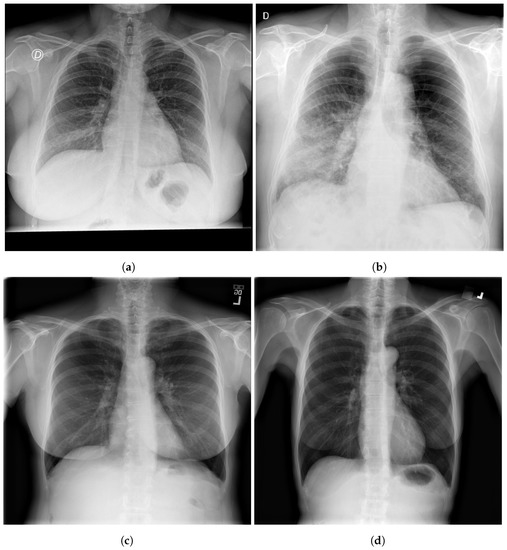

Figure 2. Examples of CXR images; SIIM-COVID-19: (a,b) and RSNA: (c,d).